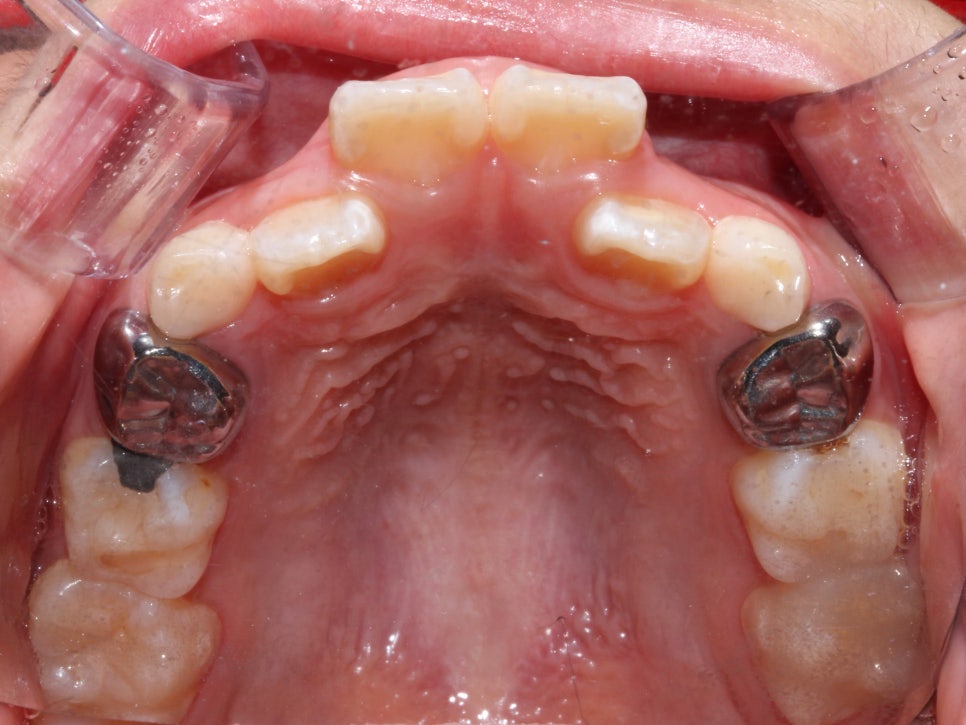

환자분의 상태를 살펴보면

치아가 날 공간이 부족하거나 치아가 나오는 방향에서

앞니가 앞으로 나오고 다른 치아가 기울어지면서

거꾸로 물리는 현상이 발생한 걸로 보여요.

상하악 Clippy-C (클리피씨) 전체 교정

구치부 반대교합은 통상적으로 비발치 교정일 경우에는

1년~1년 반 정도 교정 기간을 생각하고 있었어요-:D